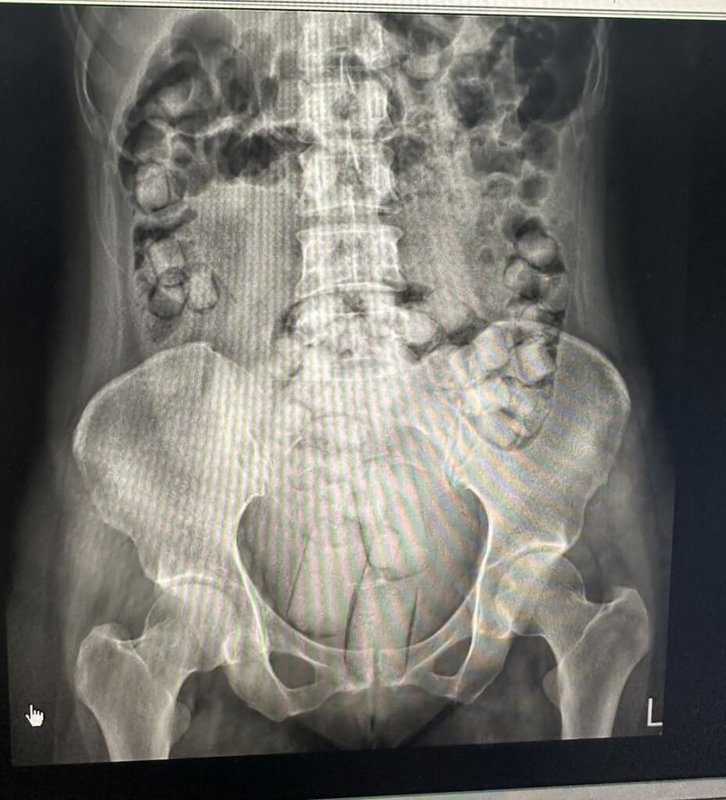

2泰女因經濟困頓且不熟悉法律,遭運毒集團以高額酬勞誘惑利用,由販毒集團將海洛因毒品分裝可供吞食的橢圓形顆粒或方便塞入私密處的長條狀,再以保險套或乳膠膜等耐腐蝕性及防水的外袋包裹後,提供運毒犯嫌分別以口服吞食及塞入肛門等方式將毒品夾藏體內規避安檢。

專案小組掌握2泰女的航班動態攔查毒品,2女被帶到高雄小港醫院排出毒品,2人分別吞食54顆、61顆海洛英毒品,共計664公克,市價約新台幣830萬元,約可供2萬5000人吸食。